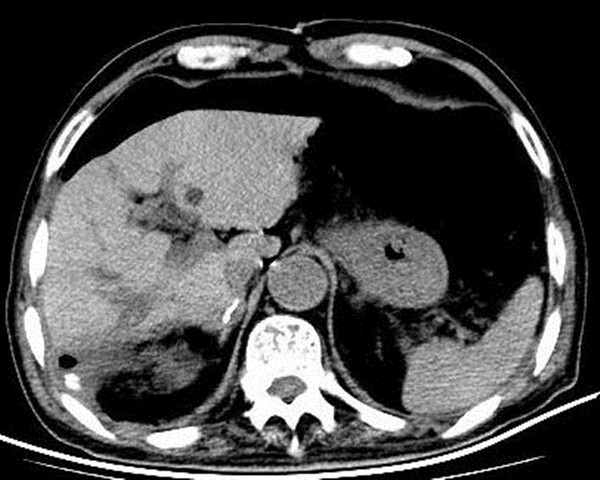

术前经过系统评估,患者存在肝硬化,肝功能属Child B级且ICGR15 20%,考虑到肿瘤的根治性,规则性肝切除是首选手术方案。术前三维重建提示若行右半肝切除,剩余肝体积仅占标准肝体积的36%,患者手术耐受性极差,术后肝功能衰竭风险极高。面对患者及家属无助的眼神,陆宏伟教授团队毅然接受了这次挑战。为了保证手术安全,决定先行保肝一周观察,在一周的保肝治疗后患者肝功能状况出现明显好转,评估达Child A级,但考虑到ICGR15仅为20%,按照右半肝切除其剩余肝体积应占标准肝体积的至少60%,术后肝衰风险仍然极高。陆宏伟教授团队展开详细术前小组讨论,在影像学评估的基础上,结合苏黎世大学和东京大学的肝切除限量标准,最终决定行解剖性的肝段切除,即Ⅵ、Ⅶ段和Ⅴd、Ⅷd亚段切除。术中在麻醉团队张晓琴教授、李伟教授和杨毅猛主治医师的保驾护航和手术室郭宁护师和刘儒忠护士的精密配合下,行经超声引导精准目标肝段切除。手术历时4小时,术中出血约300ml,术后未出现小肝综合征等肝功能不全表现,目前患者病情平稳,康复顺利,拟近期出院。

术前3D评估 手术示意图